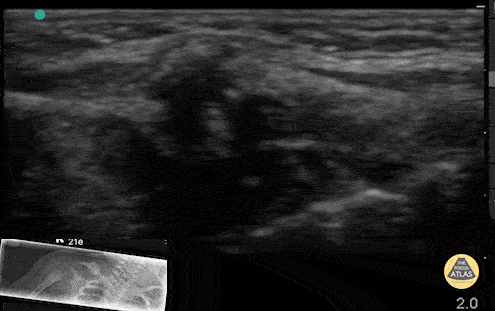

2 week old with clavicle fracture from birth trauma. Note the rounded, bony protrusion with disruption of the cortex seen by ultrasound and callous formation seen on x-ray. Contributor: Antonio Riera, MD